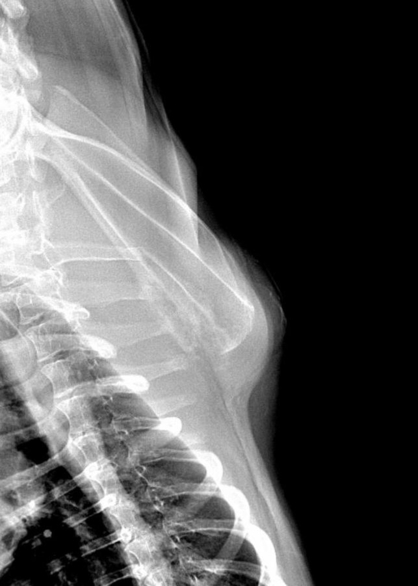

L’examen clinique révèle une masse sous cutanée de près de 10 centimètres de diamètre, localisée au niveau de la scapula (fig. 1). La palpation est indolore. La masse apparait ferme, de consistance osseuse, non mobilisable sous la peau.

Un examen radiographique est réalisé sur animal vigile. Le coude gauche présente une dégradation arthrosique déjà avancée que l’on retrouve également sur le coude droit. Une déformation des tissus mous est visible en regard de la portion caudale de la scapula. L’articulation scapulo-humérale ne présente pas d’anomalie, seule la scapula présente des modifications de son architecture sur sa face interne avec une corticale effacée, une association d’ostéolyse et d’ostéoproduction (fig. 2 et 3).